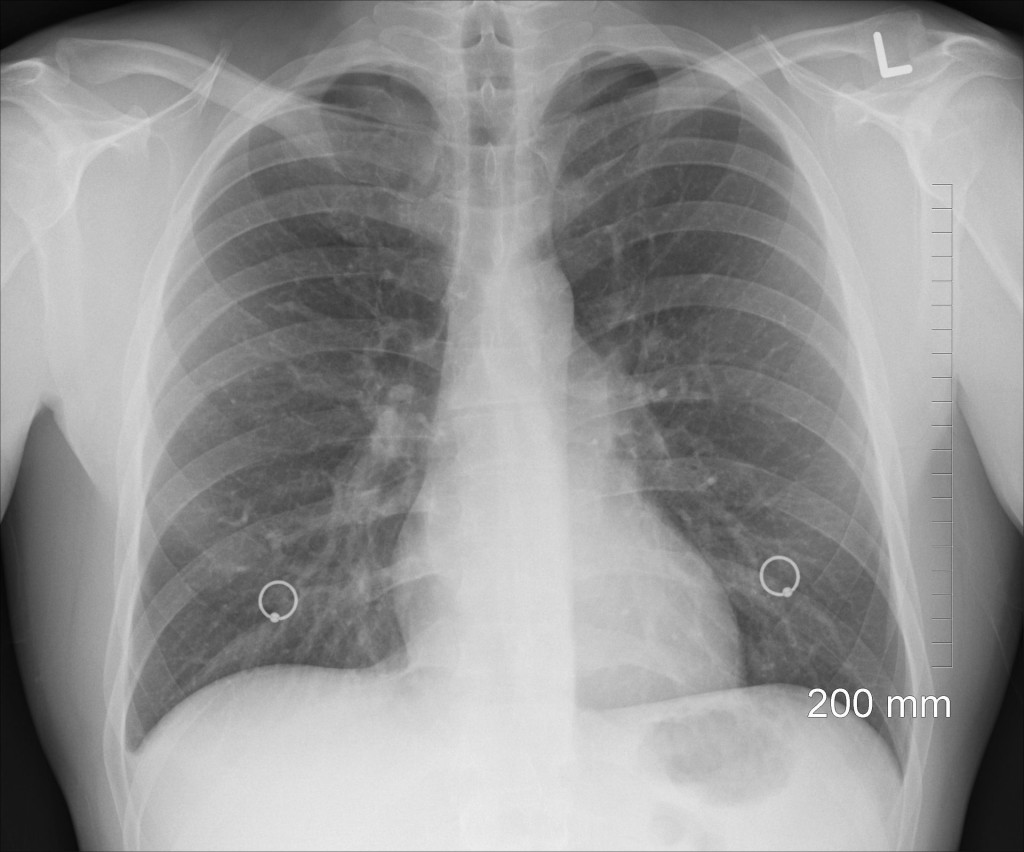

Over protonpompremmers bestaat observationeel onderzoek dat suggereert dat het gebruik ervan geassocieerd is met een grotere kans op longontsteking. Ook de NHG-Standaard Maagklachten maakt daar melding van, in verband waarmee chronisch gebruik wordt ontraden. Engelse onderzoekers gingen nu op ingenieuze wijze na of de associatie niet zou kunnen berusten op confounding.

Ze selecteerden willekeurig 160.000 nieuwe gebruikers van protonpompremmers uit een grote eerstelijnsdatabase en keken naar het optreden van pneumonie. De verkregen gegevens werden vergeleken met die van een gematchte controlegroep die geen protonpompremmer gebruikt had. Daarnaast werd bij de gebruikersgroep zelf gekeken of de kans op een longontsteking de eerste dertig dagen na de start van protonpompremmergebruik groter was dan tijdens de dertig dagen voor gebruik of de daaraan voorafgaande periode, waarbij laatstgenoemde periode werd gebruikt als referentie.

Verrassend zijn vooral de cijfers over het optreden van pneumonie binnen de gebruikersgroep zelf. De voor leeftijd gecorrigeerde incidentie van pneumonie in de dertig dagen voor protonpompremmergebruik is 1,92 maal groter dan tijdens de referentieperiode, terwijl die in de dertig dagen na de start van het gebruik slechts 1,19 maal zo groot is (beide significant).

De associatie van protonpompremmergebruik met pneumonie is dus niet langer reden  om chronisch gebruik te ontraden. Mensen die een protonpompremmer krijgen, hebben om niet geheel opgehelderde redenen vooraf al meer kans op longontsteking.